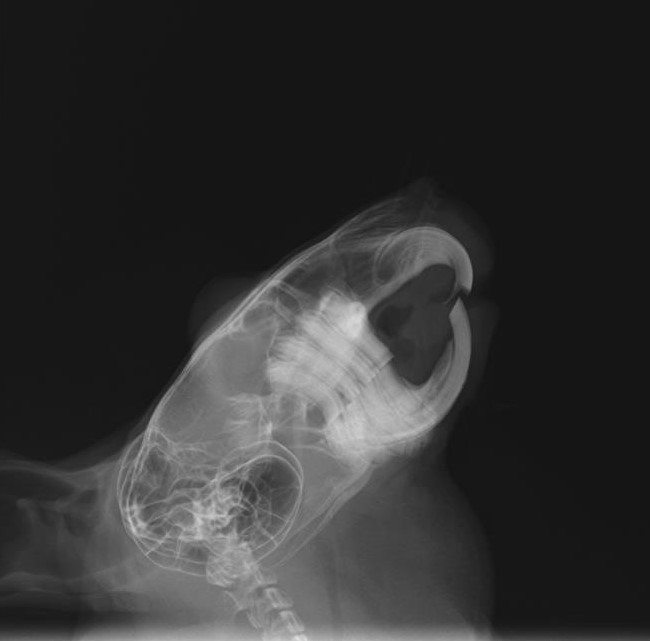

- レントゲン検査

ウサギの切歯不正咬合および臼歯過長整復